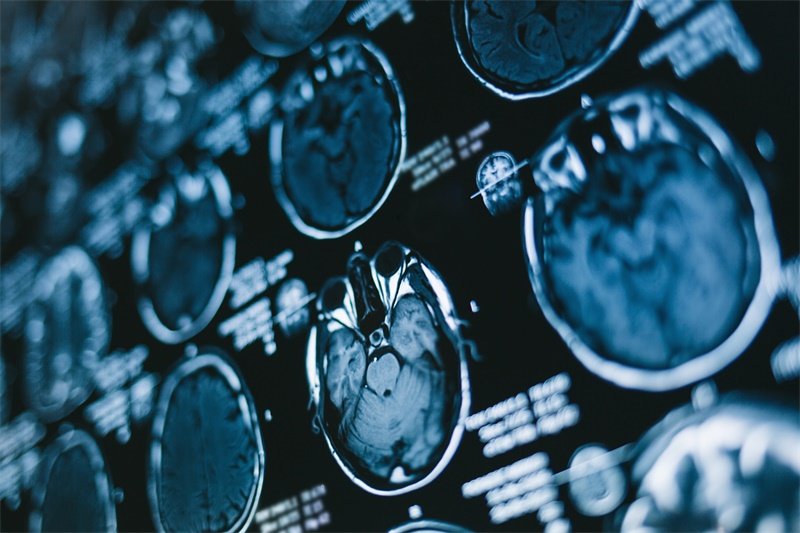

确诊垂体占位病变通常需要借助多种检查技术。例如,磁共振成像(MRI)是最常用且有效的检查方法,能够清楚地显示垂体及其周围结构的情况。此外,内分泌功能测试也是不可或缺的一部分,以帮助医生判断激素水平是否正常。

MRI检查

MRI检查能够提供关于垂体及其周围组织非常详细的影像资料。医生可以根据影像判断病变的性质和大小,并做出相应的治疗计划。对于患者而言,MRI检查是一种无创的影像学检查,过程相对安全、快速。